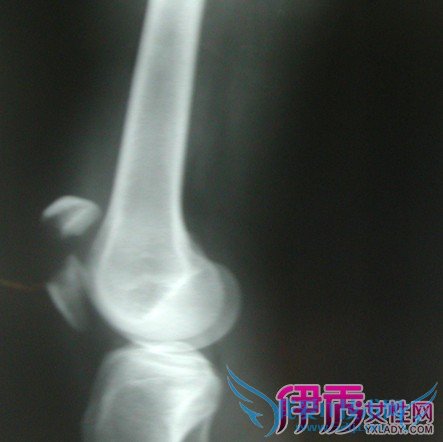

膝盖髌骨骨折的康复及注意事项 小编为你分解细节【图】

膝盖髌骨骨折的康复及注意事项